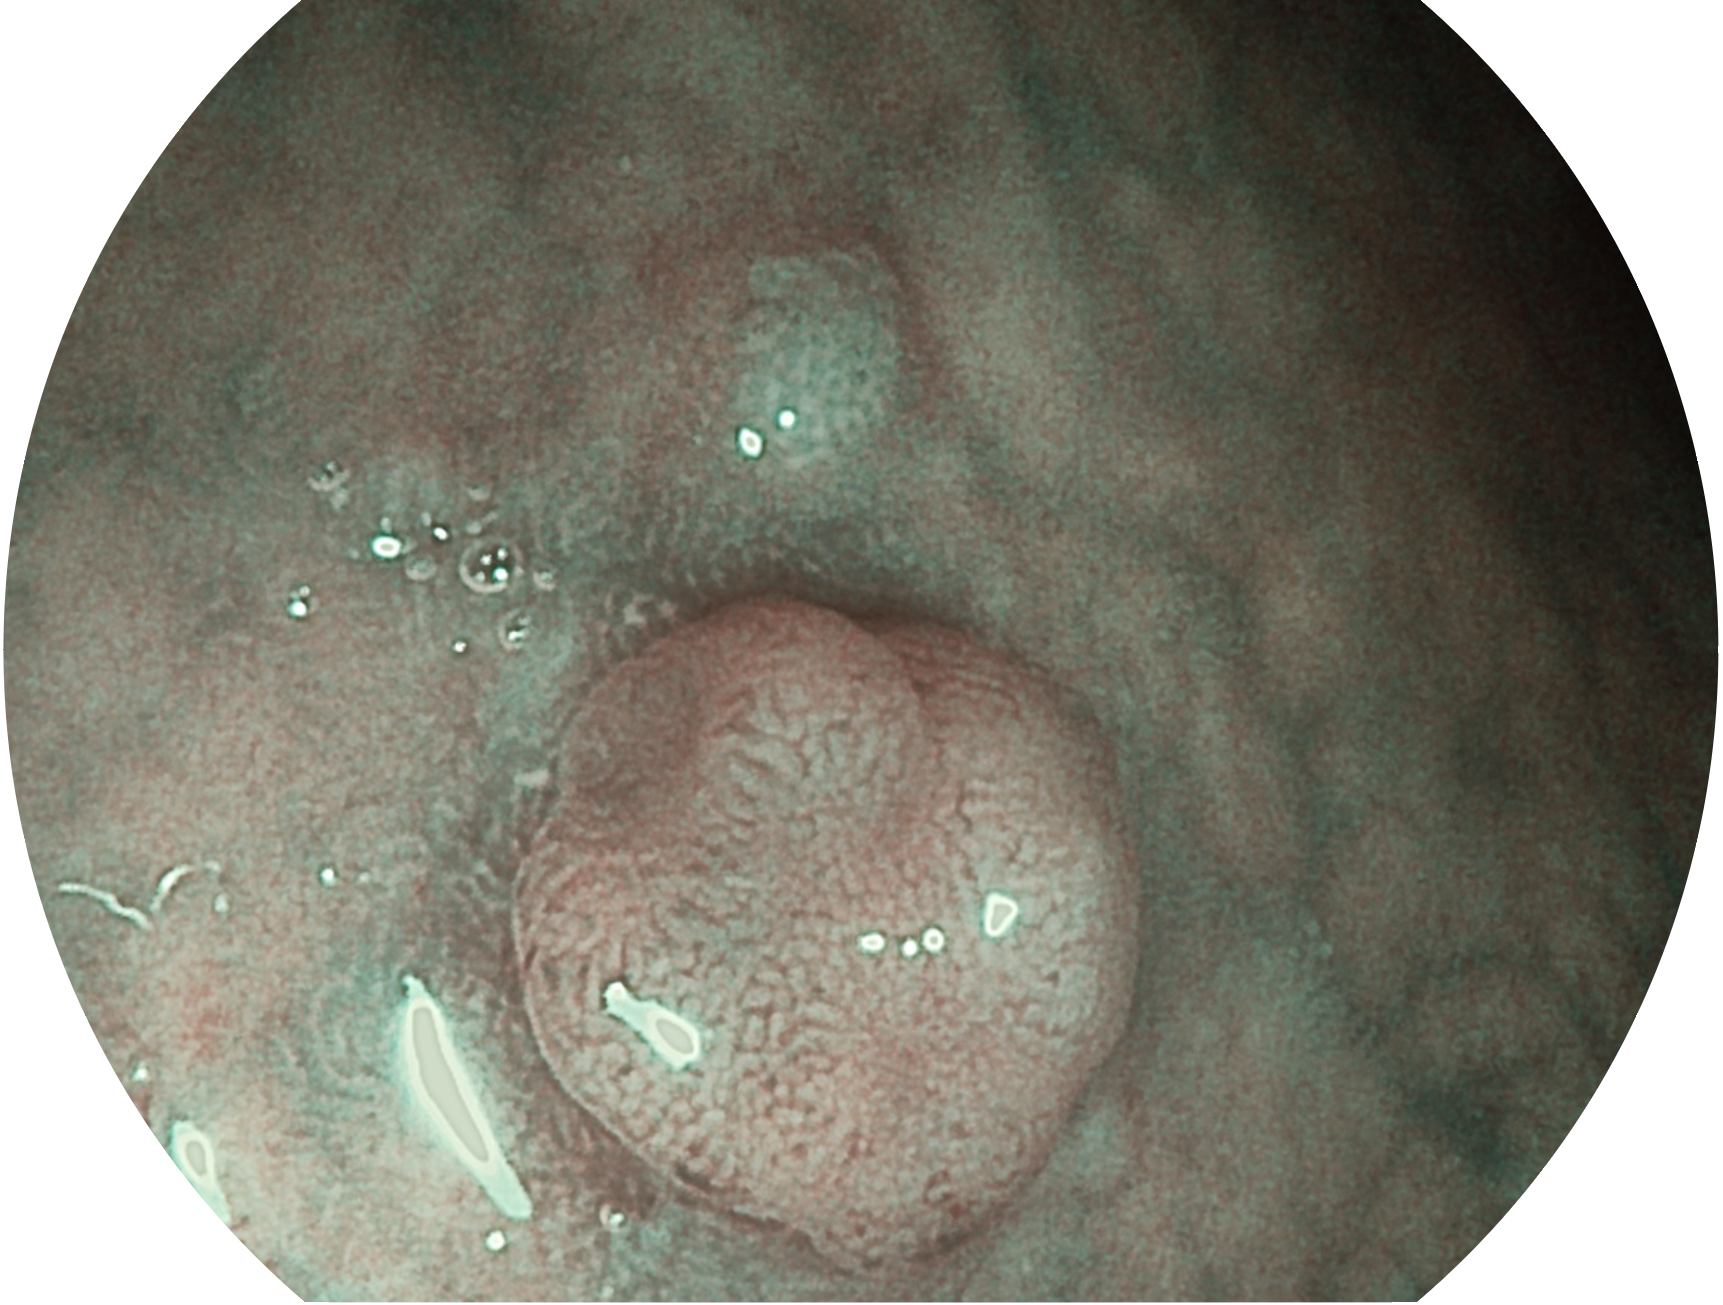

乐玩lewin国际新开发的内镜染色技术,主要是基于多波长LED 光源的开发,VLS-55Q 四波长LED 光源是由四个不同颜色的LED光按照相应照明模式所规定的特定发光比例进行合束后形成,合束后形成的照明光的光谱由红光、绿光、蓝光及蓝紫光这四个不同的波段范围构成。具有更高光谱自由度,通过光谱比例的控制,实现了聚谱成像技术,英文全称为“Spectral Focused Imaging, SFI”,缩写为“SFI”和光电复合染色成像技术,英文全称为“Versatile Intelligent Staining Technology, VIST”,缩写为“VIST”。